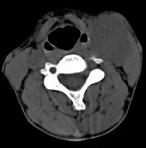

问题 女,39岁,左颈部可扪及一肿块,无发热,无疼痛,CT如图所示,最可能的诊断是()

选项 A.颈部神经鞘瘤 B.颈动脉体瘤 C.颈部神经纤维瘤 D.颈部海绵状血管瘤 E.颈动脉瘤

答案 B